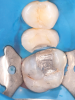

Fig 1 through Fig 5. Single-visit restoration of a maxillary second premolar following root canal treatment. Fig 1: Morphology-guided overlay preparation. Fig 2: IOS bite registration via imaging of buccal tooth surfaces. Fig 3: Preparation margin defined following IOS impression. Fig 4: Overlay design on the IOS platform, integrating adjacent tooth anatomy. Fig 5: Bonded overlay fabricated from CAD/CAM resin-based composite. Fig 6 through Fig 9. Digital workflow for guided endodontics using a digital twin, created by registering an IOI with CBCT data.

Figure 3

Figure 4

Figure 5